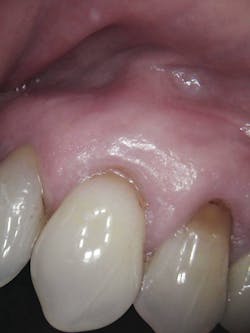

From a patient perspective, a 9.3 µm CO2 laser can dramatically change the dental experience. In this case, chair time was reduced (compare 40 minutes using the laser to the 60–90 minutes required by traditional dentistry), and the patient did not have to worry about excessive blood or postoperative pain. Healing was also rapid without any gingival defects.

During post-op visits, final results at the three- and eight-month marks and x-rays taken at eight months revealed optimal outcomes that met the clinical objective (figures 8–10).